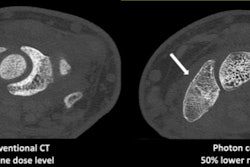

Is there an end in sight to the ongoing shortage of iodinated contrast media? Hopeful signs emerged this past week as GE Healthcare announced that a manufacturing plant in Shanghai, China, is expected to be close to full production capacity the week of June 6.

The disruptions have affected supplies of GE's Omnipaque and Visipaque contrast agents, and they began after a series of lockdown measures imposed by Chinese authorities in Shanghai interrupted manufacturing at the plant. This has had a ripple effect, particularly in the U.S., and many radiology facilities have had to triage some imaging exams to conserve contrast supplies.

It may take some time for radiology to get back to normal. And over the long term, questions remain as to whether hospitals and imaging centers will take the steps necessary to mitigate the impact of supply chain disruptions in the future.